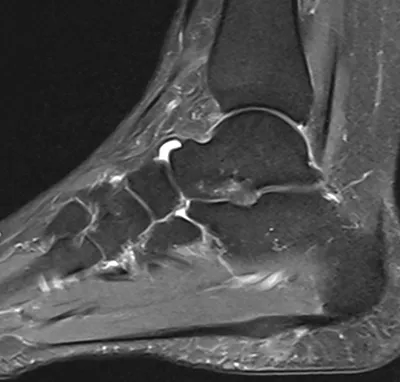

This collection contains 3 radiology images related to plantar fascia, including various imaging modalities such as X-rays, MRIs, CT scans, and ultrasound images commonly used in medical diagnosis and education.